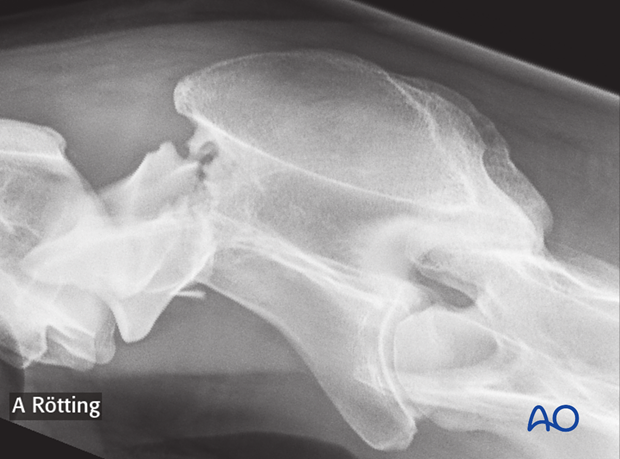

The radiograph shows the fracture of the dens in a foal.

Fractures of C2 (Axis) can occur in the axial dens (a) or the axial body (b), with or without involvement of the spinal canal.

This fracture is most commonly seen in foals younger than 6 months: